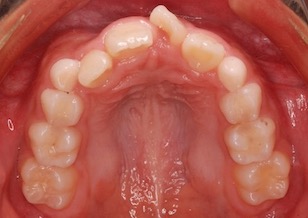

Before Ⅰ、Ⅱの写真は、初診時の口腔内写真です。

上下顎歯列に叢生(ガタガタの歯並び)を認めます。